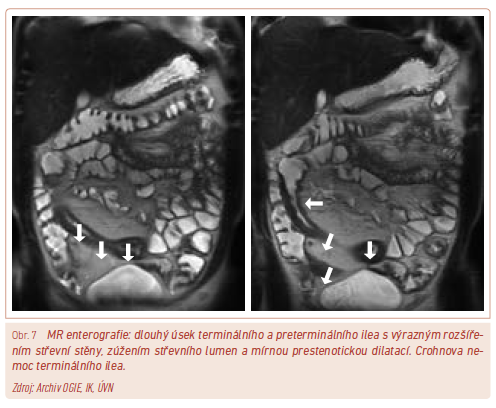

MR enterografie

Využití MR v diagnostice IBD je vzhledem k absenci radiace stále častější. Primárním využitím magnetické rezonance je určení rozsahu zánětlivého postižení střeva, které nelze vyšetřit endoskopicky. Metoda je schopna hodnotit transmurální i extramurální projevy nemoci (obr. 7). Důležitou roli hraje MR v posouzení extraintestinálních projevů, resp. primární sklerozující cholangitidy, kde až na situace vyžadující drenáž žlučovodů zcela nahradila invazivní vyšetření ERCP (endoskopická retrográdní cholangiopankreatografie). Dalším využitím MR u mimostřevních projevů IBD je hodnocení sakroileitidy.18